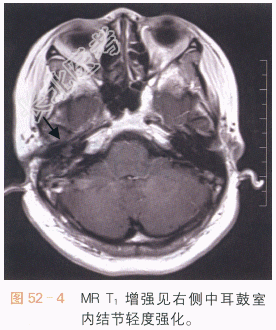

读片分析:面神经鞘瘤多见于面神经位于内耳与鼓室交界处的膝状神经节的面神经管内,它使面神经管扩大,CT扫描可见鼓室内沿后壁的软组织结节影及周围骨质的吸收或破坏,如图52-1所示,在MR图像上,面神经瘤呈等或等高信号,具轻度强化,如图52-2~图52-4所示,面神经鞘瘤主要的临床症状是面神经麻痹或面肌痉挛,可伴听力下降。由于患者临床症状出现较早,因此初次发现的面神经鞘瘤通常不大,需要我们仔细地进行影像学观察,否则容易遗漏。生长得比较大的面神经瘤,可以见到神经鞘瘤特有的囊实性结节,及其相应的影像学表现。